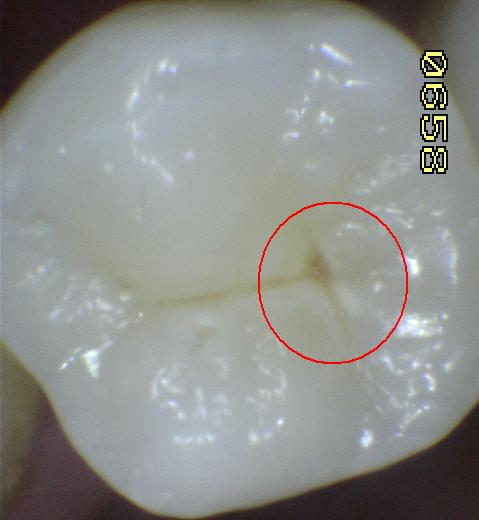

Código 4